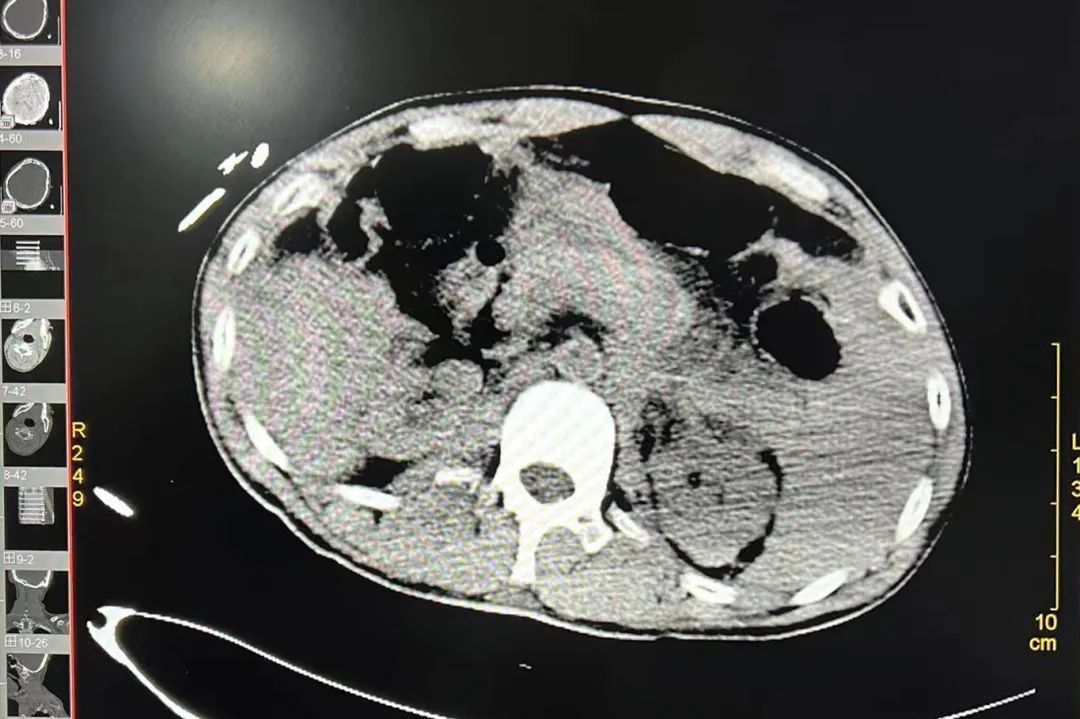

榆林市星元医院立即启动急危重症绿色通道及应急预案,急诊科迅速进行抢救,手术室同步进行相关术前准备,经过超声、CT检查,患者被诊断出创伤失血性休克、急性弥漫性腹膜炎、脾破裂、左肾碎裂、空肠多处破裂、结肠破裂、胃窦破裂、胰尾断裂、多发肋骨骨折、创伤性湿肺、蛛网膜下腔出血、脑挫伤伴出血、右侧颞骨骨折等。